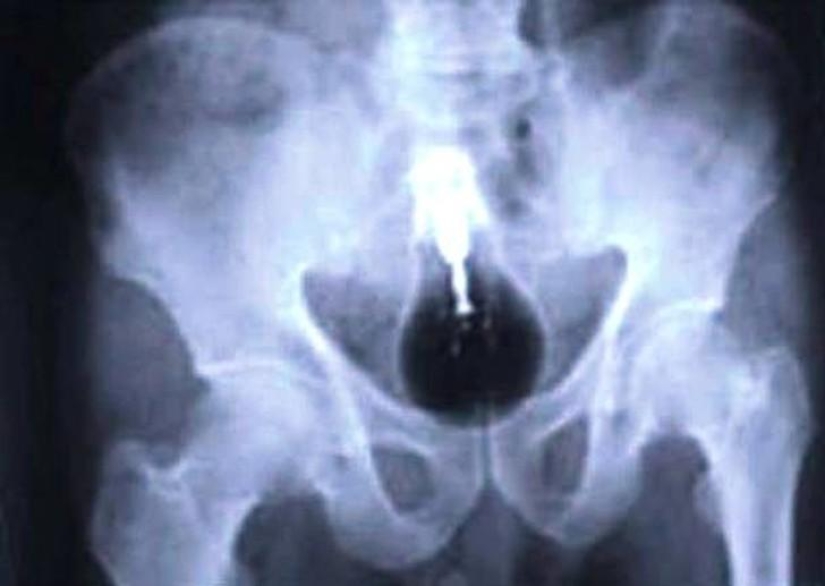

Bulbo.